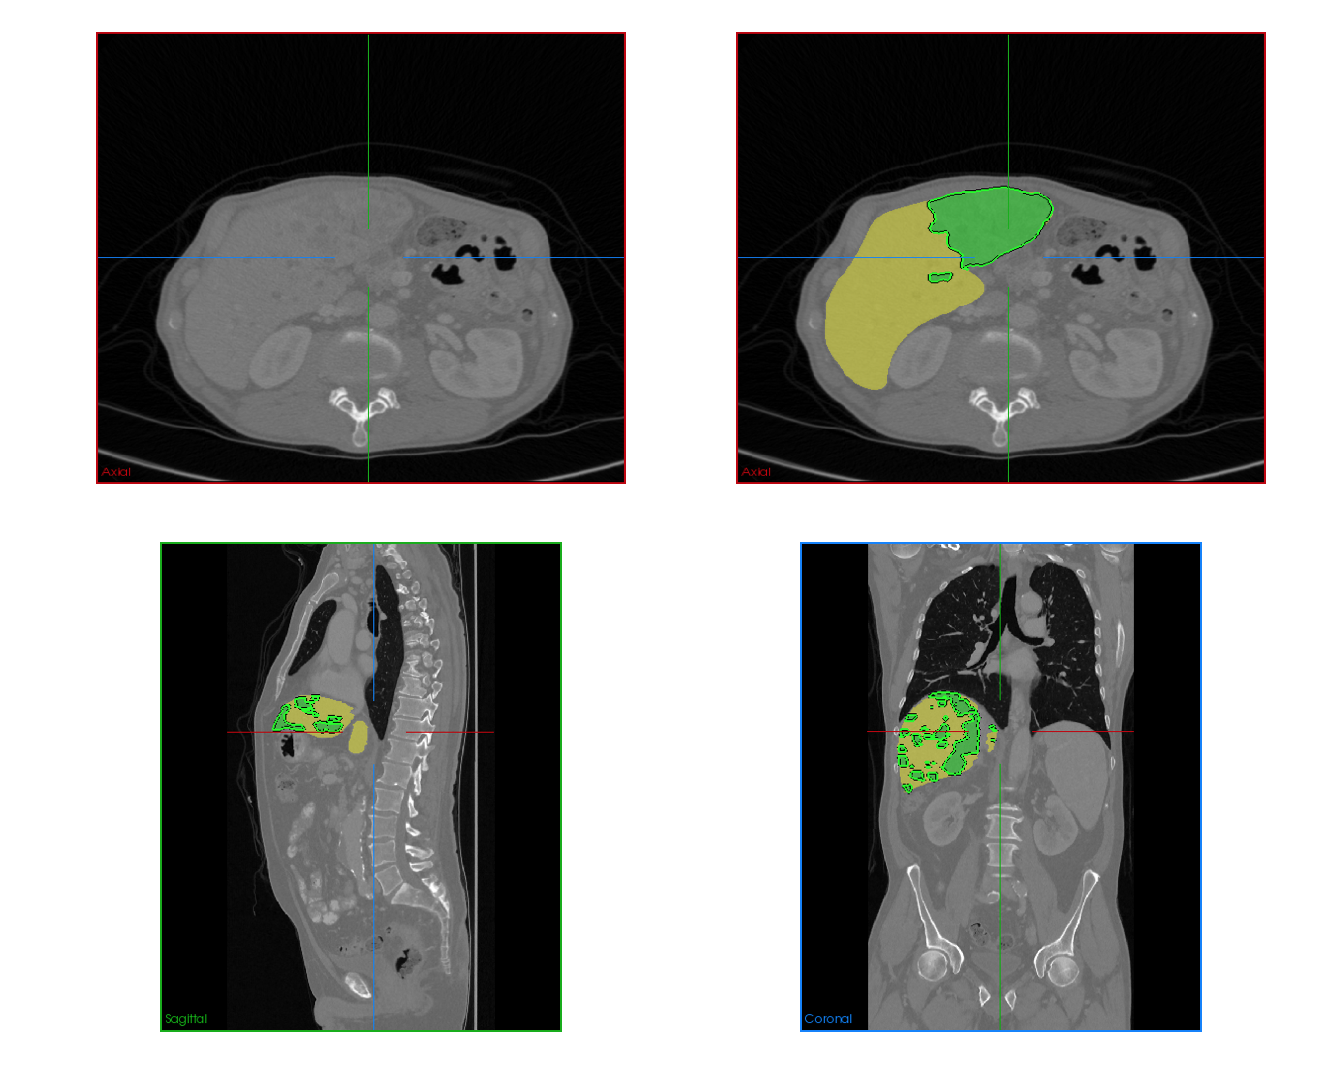

This challenge includes liver segmentation and liver tumor segmentation. The dataset consists of 131 training datasets and 70 testing datasets, all of which are 3D abdominal CT scan images that contain liver. Label maps (annotations) are provided for the training data, but not for the testing data. Participants are required to train their model on the training data, then use the well-trained model to make predictions for the testing data. The prediction can be submitted back to the orgnizer for blind evaluation. An example 3D CT data visualized in different directions is shown in Figure 5.

Refer to caption

Figure 5: Different positions of an example 3D CT data. Upper left: oblique coronal position. Upper right: add annotation (label) to the upper left image, where yellow area is the liver, green areas are the tumors on the liver. Lower left: sagittalia position; lower right: oblique-axial position.